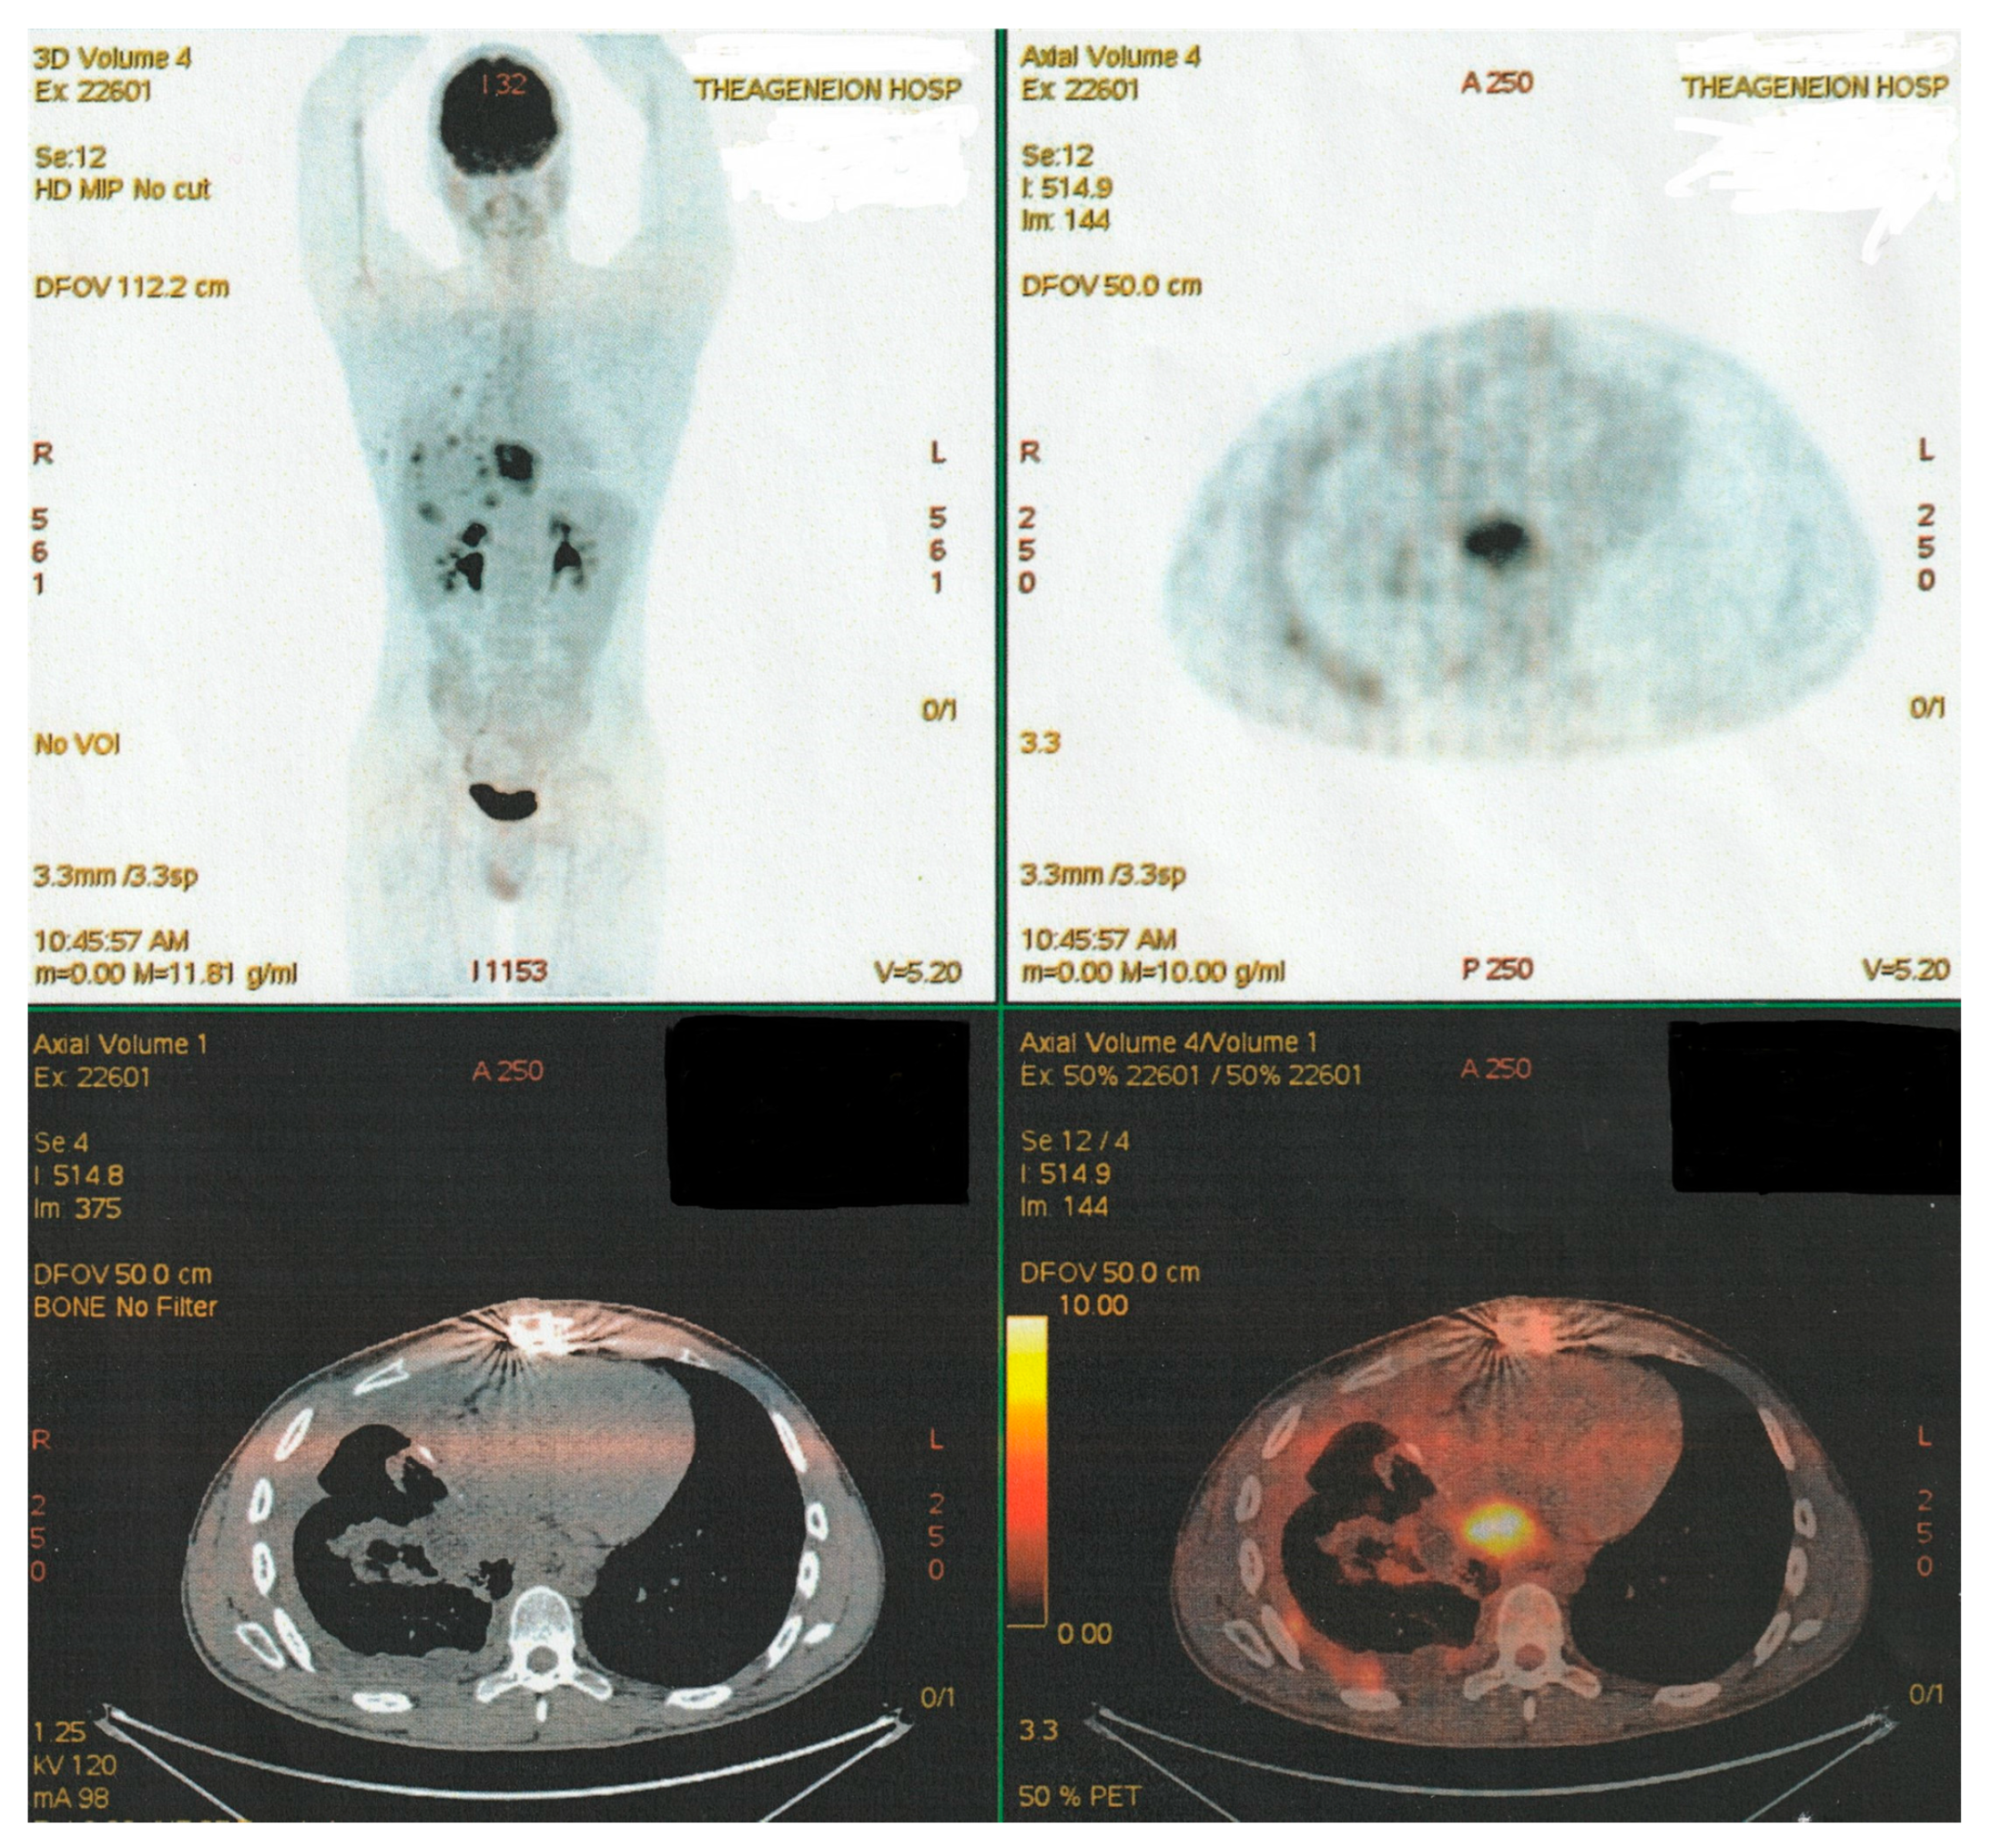

PET-CT imaging controls at multiple intervals, specifically after the third and sixth scheme course, revealed elements of stable disease evolution. Radiologic data indicated a decrease in metabolic activity in the mediastinum and hepatic hilar lymph nodes, hepatic parenchymal secondary lesions, the size of the retrocardiac mass and diameter of the (R) lung infiltrates, as well as the stabilization of osseous lesions {(R) femur, T10, L2, and L3 lesions}, though some residual metabolic activity remained persistent for a while (Figure 12).

Figure 12. Latter PET-CT imaging control (after six “TIP-Regimen” sessions).